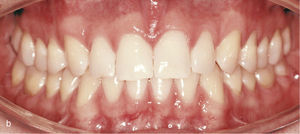

EspaciosEl cierre de espacios en el sector anterior se clasifica dentro de los movimientos dentales sencillos con el sistema Invisalign. En la vista intraoral de la figura 6a se observan sendos sectores anteriores con espacios en maxilar y mandíbula. Se realizó el cierre de los espacios y también la intrusión de los dientes 11 y 21. Con dicho fin fueron adheridos ataches rectangulares en los dientes 13, 23, 11 y 21. La imagen intraoral de la figura 6b muestra el resultado del tratamiento después de cerrar los espacios y de reducir la sobremordida vertical.

Vista intraoral de los dientes anteriores separados entre sí y de los ataches en los dientes 13, 11, 21 y 23 para el cierre de los espacios y también en los dientes inferiores 33, 34, 35, 43, 44 y 45 para obtener el anclaje necesario para la intrusión de los dientes anteroinferiores (a). Vista intraoral del resultado después del cierre de espacios y de la creación de una sobremordida horizontal y vertical fisiológica (b).